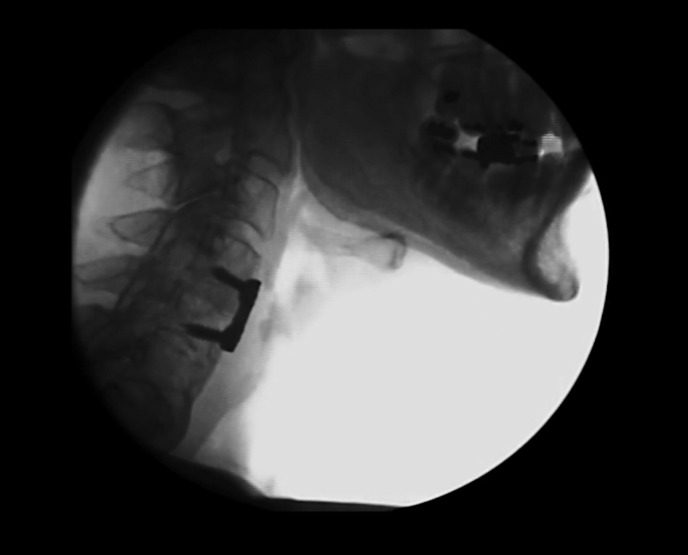

Case presentation: An 83-year-old male experienced dysphagia >2 months post-ACDF. The patient presented with a narrowed pharyngoesophageal segment due to cervical hardware and reduced epiglottic inversion due to pharyngeal narrowing on videofluoroscopic swallow study (VFSS). He completed dysphagia therapy using neuromuscular electrical stimulation (NMES). Structural alterations and a complicated medical course after treatment impacted therapeutic outcomes. Reductions in penetration or aspiration and improved hyoid excursion were found post-treatment, though impairment persisted. The patient ended therapy after the post-treatment VFSS and began to experience odynophagia and submental pain. The patient experienced a complicated post-treatment course including bilateral cancerous masses at the base of tongue with subsequent surgery and chemoradiation.